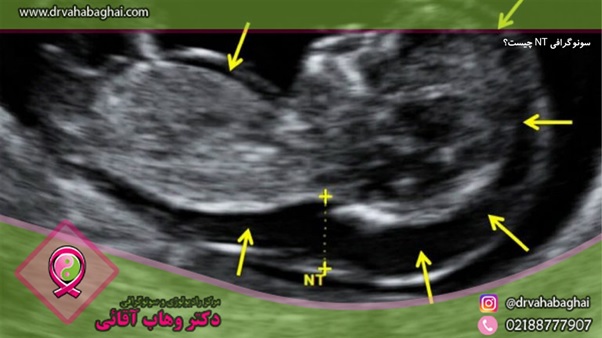

اصطلاحNT  مخفف Nuchal translucency می باشد. سونوگرافی NT، یک روش نوین و غیر تهاجمی می باشد. در این روش با اندازه گیری میزان مایع در پشت گردن جنین به همراه اندازه گیری دو فاکتور در خون مادر، با در نظر گرفتن سن مادر به انضمام سن جنین و ضربان قلب جنین، ریسک نسبی بعضی از بیماری ها و آنرمالی ها تعیین می شود.

در طول غربالگری، پزشک یا تکنسین، یک سونوگرافی شکم می گیرد. این تست را می توان به صورت ترانس واژینال انجام داد که در آن یک پروب اولتراسوند از طریق واژن وارد بدن می شود. در سونوگرافی از امواج صوتی با فرکانس بالا، برای ایجاد تصویری از داخل بدن استفاده می شود. با استفاده از این تصویر، پزشک یا تکنسین شفافیت یا فضای خالی پشت گردن کودک را اندازه گیری می کند. سپس سن یا تاریخ تولد مادر را در یک برنامه رایانه ای وارد کنند تا خطر ابتلای کودک به ناهنجاری های مختلف را محاسبه کنند.